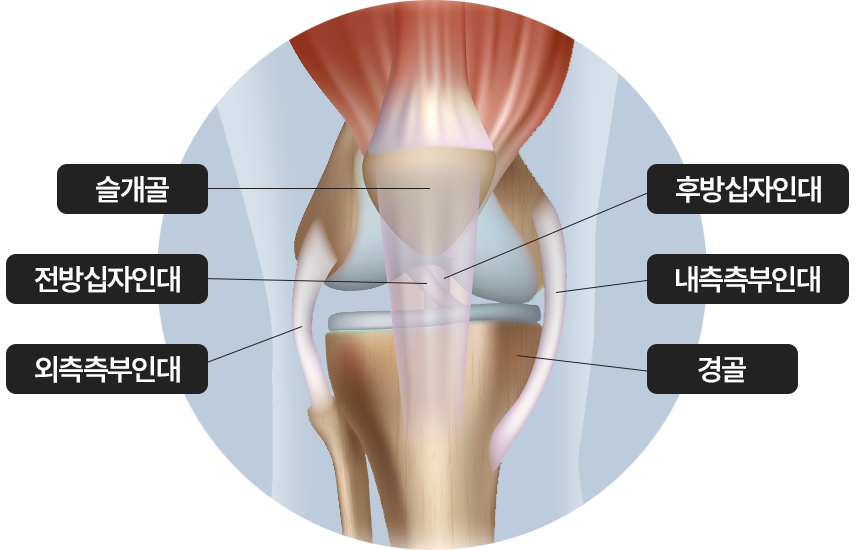

무릎 인대 손상

무릎관절의 큰 충격, 과도한 회전, 갑작스러운 움직임으로 인해 전후방 십자인대나

측부 인대 손상

완전 파열이 아니면 보존적 치료로 호전 가능

슬개골 / 전방십자인대 / 외측측부인대 / 후방십자인대 / 내측측부인대 / 경골